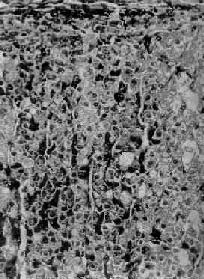

图15-14 肾上腺皮质弥漫增生

图15-13之镜下观,肾上腺皮质束状带弥漫性增厚